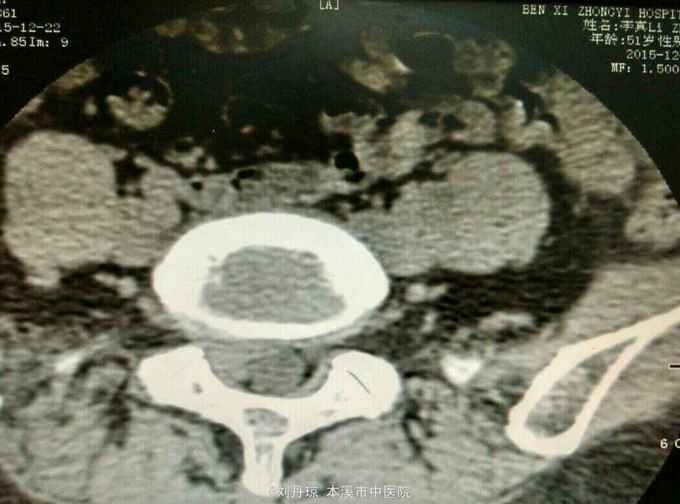

查体:L5—S1棘突旁压痛阳性。直腿抬高实验。左70度,右30度。加强试验左侧阴性,右侧阳性。腰椎功能障碍。CT:L5—S1椎间盘突出。

诊断:腰椎间盘突出症 治疗:针灸、雷火灸、中药熏药治疗、小针刀治疗、骶管注射治疗、营养神经药物治疗、脱水药物治疗,当归地黄饮加味。